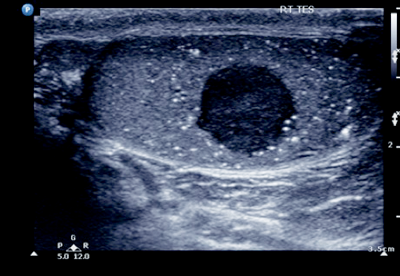

Case 1

- What does the ultrasound show?

-

Right-sided testicular mass with associated microlithiasis.